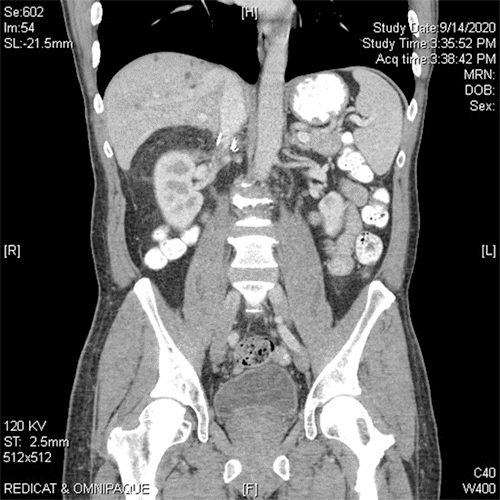

Figure 3. Gross Cross-section of Right Adrenal Mass. Published with Permission

Green arrow: neoplasm; Purple arrow: surrounding hemorrhage within the adrenal

The pathology result for the right adrenal tumor was epithelioid angiosarcoma with extensive surrounding hemorrhage, with negative tumor margins and an intact capsule. Consultation with the Department of Pathology at Brigham and Women’s Hospital confirmed this diagnosis, showing atypical endothelial cells with epithelioid morphology, amphophilic cytoplasm, and vesicular nuclei. The specimen stained positive for CD31 and ERG (ETS-related gene, an oncogene). Figure 1 shows cross-sectional imaging of the abdomen before and after the surgery. Figures 2 and 3 show the gross specimen (green arrows point to the tumor, and the purple arrow to the associated hematoma). Figures 4 and 5 show the microscopic histopathologic view of the specimen (green arrow points to the atypical endothelial cells, purple arrow to the hematoma).